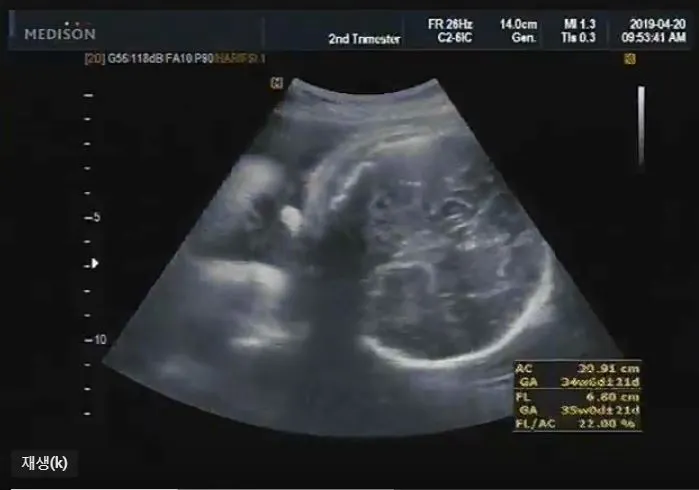

짠짠이 29주 ~ 36주 차

29 ~ 36주.

아내는 날이 갈수록 점점 배가 불러갔고 짠짠이는 엄마 뱃속이 좁다고 매일 난리다. 초음파 사진 모습도 대강 비슷해서 항상 "좁다!!!"라고 하는 것 같다. 엄마 배를 뻥뻥 차서 아내는 잠도 깨고 어떨 때는 아프기까지 했다고. 아내는 이제 정말로 몸이 무겁다는 말을 실감했다. 짠짠이는 자리를 잡아 걱정이 없는데 아내는 뭘 해도 피곤하고 몸이 붓고 뼈마디가 쑤시기 시작했다. 그래도 짠짠이가 나오기 전에 둘만의 시간을 만끽하러 무거운 몸을 이끌고 열심히 다녔다. 여러 가지 모습으로 짠짠이를 맞이할 준비를 하던 시기.